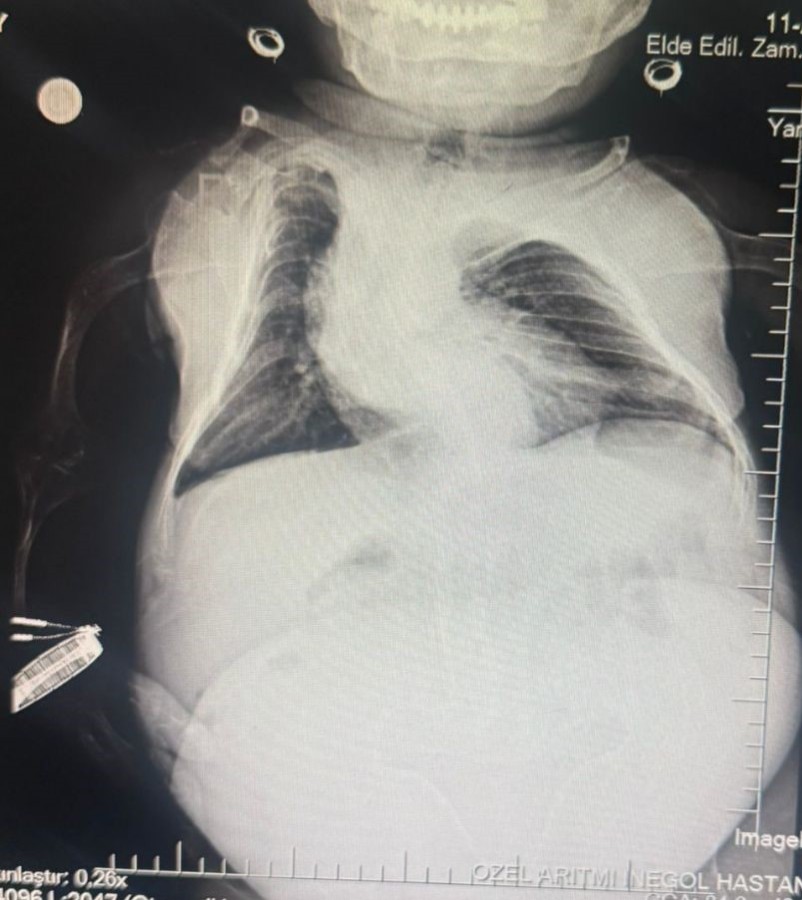

Halk arasında cücelik olarak bilinen Akondroplazi rahatsızlığı ile dünyaya gelen 30 yaşındaki Nurdan Tüfekçi, son 1 yıldır yaşadığı karın ağrısı şikayeti nedeniyle birçok hastaneye başvurarak tedavi gördü. Son olarak İnegöl'deki özel bir hastanenin kadın hastalıkları bölümüne başvuran 80 santim uzunluğunda ve 24 kilogram ağırlığındaki Nurdan Tüfekçi'nin yapılan tetkiklerinde yumurtalığında 3 kilogram kist olduğu tespit edildi. Hasta hemen ameliyata alındı. Belinden yapılan anestezi ile uyanık şekilde 1.5 saat süren ameliyatı başarılı geçen Tüfekçi, 3 kilogram olan kistten kurtulması ile 24 kilogramdan 21 kiloya düştü.

Anestezi Doktoru Mahmut Gül, "Hastamız 30 yaşında. 80 santimetre boyunda, 24 kilo ağırlığında bir kardeşimiz. Kendisinin yumurtalıklarında kist olduğu için ameliyat olması gerekti. Biz bu ameliyatta hastamıza önce büyük bir damar yolu açtık kasıktan. Çünkü damar yolunun çok önemi var ve daha sonrasında ameliyat sırasında belinden uyuşturduk ve ameliyatı sorunsuz bir şekilde belden uyuşturmayla hastamız uyanık bir şekilde tamamladık. Hastadan 3 kilo kist çıktı. Öncesinde 24 kilo olan hastamız, ameliyat sonrasında 21 kiloyla şifalı bir şekilde serviste yatıyor. Ameliyatı bugün oldu. Şu anda da serviste hastamız. Bu tür ameliyatlarda uyutmak hastamız açısından oldukça risklidir. Biz o yüzden bölgesel anesteziyi yani belden uyuşturmayı tercih ettik. Literatürde çok olmayan bir hasta ve güvenli bir şekilde hastanemizde bu ameliyat tamamlandı" dedi.

Kadın Hastalıkları Uzmanı Mustafa Kır, "Hastamızda 20 santimlik tümör vardı kistlik yapıda. Onu başarılı bir operasyonla çıkarttık" şeklinde konuştu.